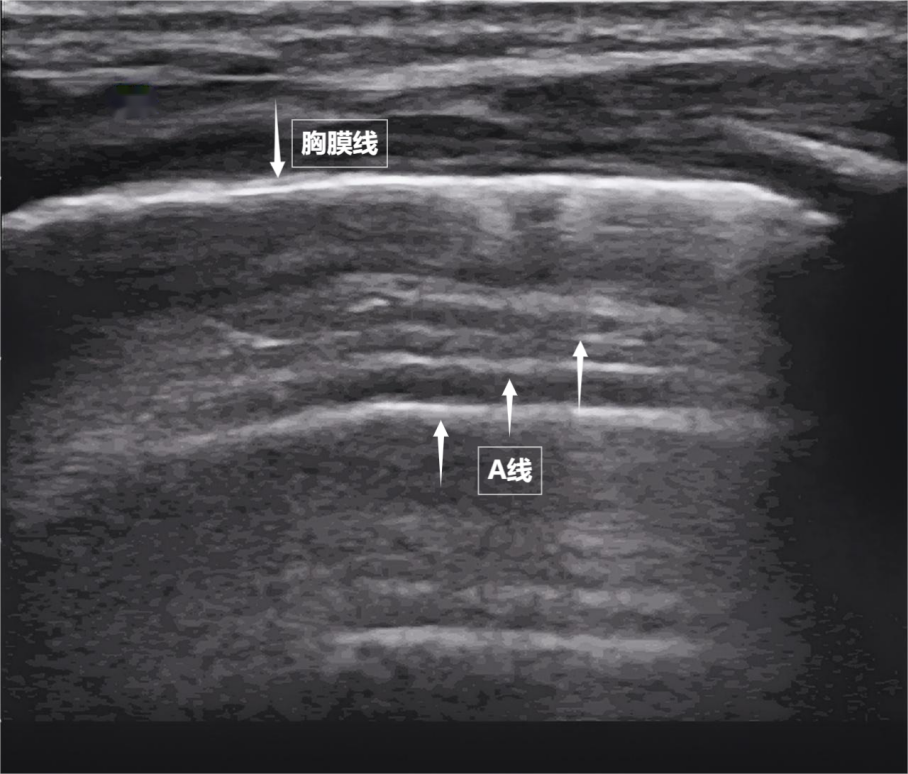

當聲波穿過胸壁肋骨縫隙,首先會遇到緊貼肺表面的光滑薄膜——壁層胸膜和臟層胸膜。兩者緊密相貼,中間沒有多余的氣體或液體。它們在屏幕上呈現(xiàn)為一條明亮、光滑的水平線,共同構成了胸膜線。這條線就是肺的“海岸線”。在它的下方,由于肺泡內(nèi)大量氣體對聲波的強烈反射,會出現(xiàn)一系列與胸膜線平行的、等間距的、重復出現(xiàn)的明亮平行線,像海浪般不斷向屏幕深處延伸,這就是A線(見下圖)。A線是正常含氣肺部的典型標志。它的存在直接提示肺表面含氣充足,胸膜腔內(nèi)無異常積液或氣體。

圖為正常新生兒肺部超聲表現(xiàn)